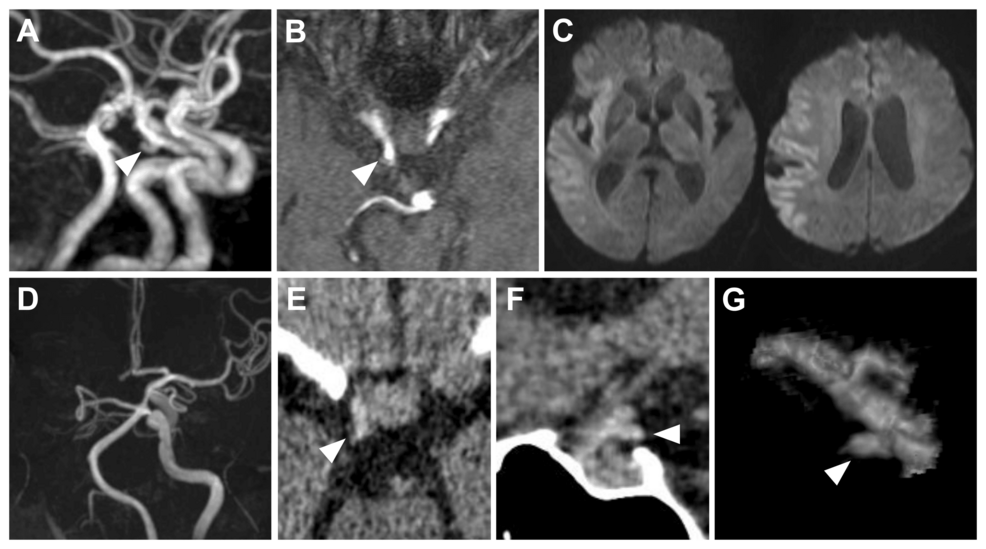

Imagine a surgeon, mid-procedure during a life-threatening stroke, suddenly able to *see* the aneurysm that caused it – not through traditional angiography, but in real-time, directly at the occlusion site during thrombectomy. This isn’t science fiction. A recent case report published in Cureus details just such a scenario, showcasing a hyperdense aneurysm visualized during mechanical thrombectomy. This breakthrough isn’t just a fascinating medical anomaly; it signals a potential paradigm shift in stroke intervention, driven by advancements in imaging technology and the increasing integration of artificial intelligence.

The case report, documenting the visualization of a hyperdense aneurysm during thrombectomy, highlights a critical challenge in stroke treatment: identifying the underlying cause while simultaneously addressing the immediate blockage. Traditionally, this requires separate diagnostic procedures, adding time and risk to an already urgent situation. **Thrombectomy**, the mechanical removal of a blood clot from a brain artery, is the standard of care for large vessel occlusions, but understanding the source of the clot – often an aneurysm – is crucial for preventing recurrence. This new visualization technique offers the potential to streamline this process, leading to more effective and comprehensive treatment plans.

The visualization described in the Cureus report wasn’t achieved with a new surgical instrument, but with a refined application of existing technology. Specifically, it leveraged high-resolution non-contrast computed tomography (NCCT) imaging during the thrombectomy procedure. However, the key isn’t just the imaging itself, but the ability to interpret the subtle nuances within the scan. This is where artificial intelligence (AI) is poised to play a transformative role.

AI algorithms, trained on vast datasets of brain scans, are becoming increasingly adept at identifying subtle anomalies – like hyperdense aneurysms – that might be missed by the human eye. These algorithms can analyze images in real-time, providing surgeons with immediate feedback and enhancing their diagnostic capabilities. Furthermore, advancements in CT perfusion imaging, which assesses blood flow in the brain, are providing a more dynamic picture of the vascular landscape, complementing the static view offered by NCCT.